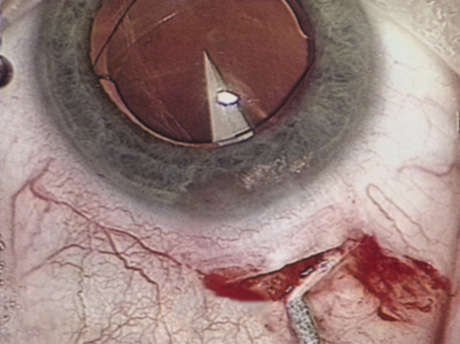

WHITE CATARACT

The introduction of innovative adjunctive devices was able to improve the management of challenging cases. The capsular tension ring introduced independently by Tsutomu Hara37 and Toshiyuki Nagamoto38 in Japan was identified as a major weapon in managing zonular weakness by Ulrich Legler and Bernd Witschel of Germany.39 The CTR came to the United States in 1993,40 after which modifications by Robert Cionni,41 Iqbalk Ahmed and Alan Crandall,42 and Burkhard Dick were developed. Iris reconstruction had been primarily limited to suture techniques developed by Malcolm McCannel43 and later Steven Siepser.44 The prosthetic irides were introduced by German surgeons, Ranier Sundmacher45 and Volker Rasch,46 and brought to the United States by Kenneth Rosenthal and then Robert Osher in 1996.47 Although many devices had been developed to mechanically open the small pupil, it was the stretch technique developed by Luther Fry that greatly simplified these difficult cases.48 Improving visibility by staining the anterior capsule of the white cataract was introduced by Masayuki Horiguchi from Japan (ICG)49 and Gerritt RJ Melles from The Netherlands (Trypan Blue).50